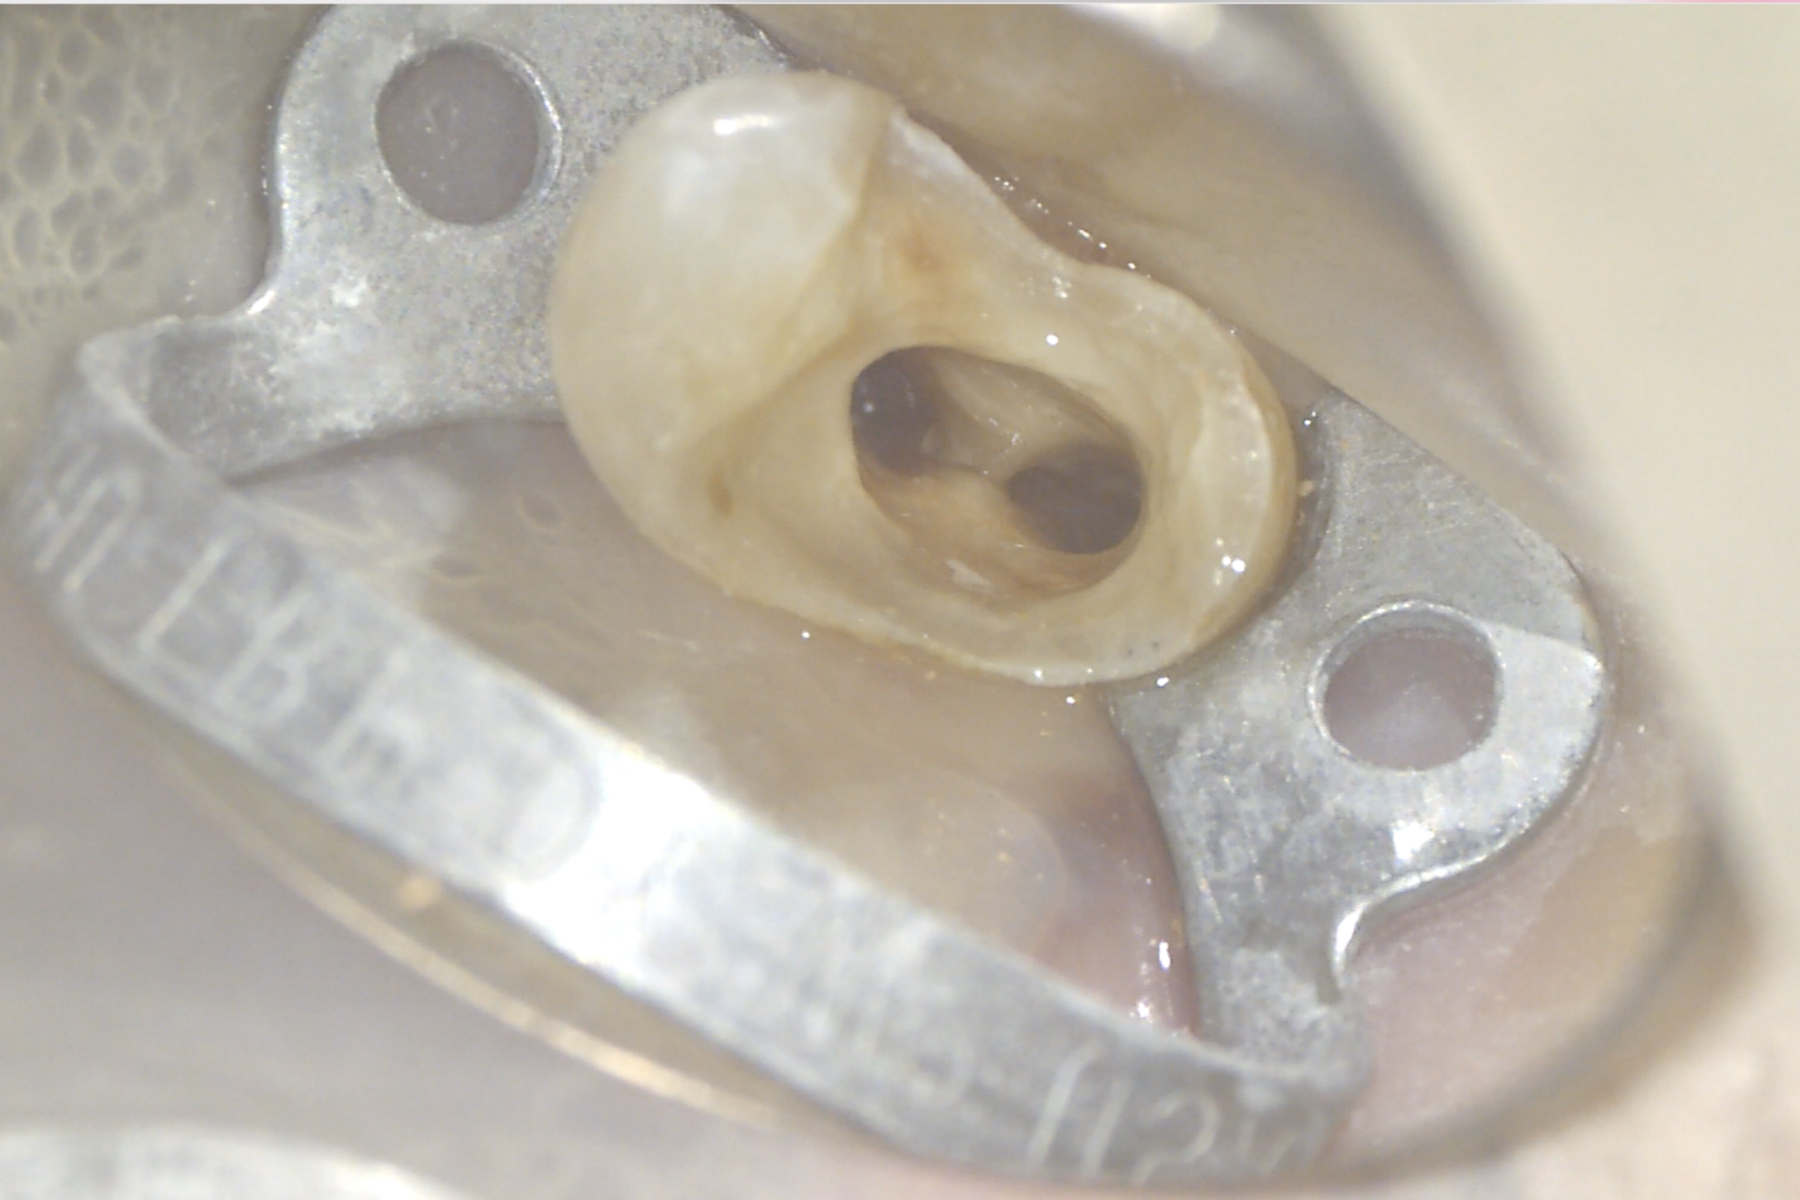

Il piano di cura proposto al paziente prevede il ritrattamento e la ricostruzione adesiva dell’elemento 25 e la successiva copertura cuspidale tramite restauro indiretto. Previa anestesia plessica si esegue l’isolamento dell’elemento mediante diga di gomma. La rimozione del restauro coronale viene eseguita con frese diamantate e abbondante irrigazione. Ultimata questa fase risultano ben visibili i perni in fibra di carbonio cementati nei canali palatale e vestibolare. La rimozione di questi ultimi viene eseguita mediante manipolo ultrasonico con inserto Start-X N.3 (Dentsply-Sirona) consumando i perni stessi e distaccando il cemento composito presente nel canale (Figure 2-3).

Visualizzata la guttaperca intracanalare con core plastico (Figura 4) viene completato lo svuotamento dei canali (Figura 5) mediante strumenti rotanti Protaper Gold (Dentsply-Sirona); effettuata la misurazione elettronica della lunghezza di lavoro, si procede con la strumentazione degli interi canali con tecnica step-down.